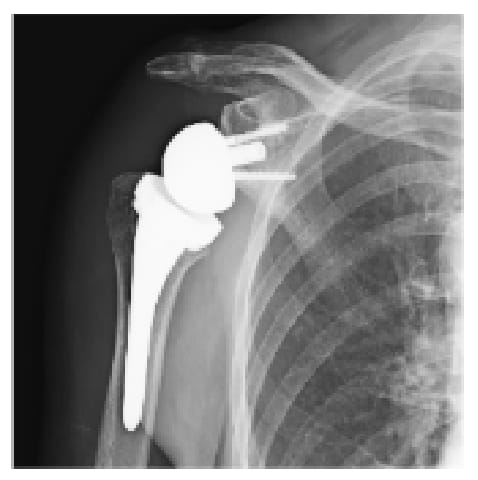

腱板断裂症性肩関節症や修復困難な肩腱板断裂に対しては、リバース型人工肩関節置換術を実施しています。良好な機能回復を得るためには、正確かつ再現性の高いインプラント設置が不可欠です。当班では、CT 画像を用いた術前3Dプランニングに加え、術中ナビゲーションシステムなど最先端の技術を活用することで、より高精度な手術を実現しています。

術中ナビゲーションシステム

術後X線